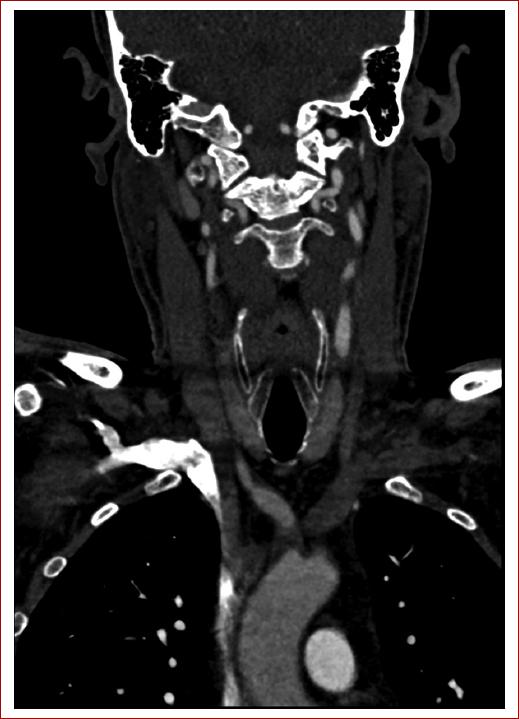

Se realiza una ecografía de troncos supraaórticos (TSA), en la cual se objetivan pequeñas placas de ateroma en ambos bulbos carotídeos. En el eje carotídeo derecho se evidencia un flujo atenuado con ascenso sistólico lento y velocidad pico sistólica disminuida. La arteria vertebral derecha muestra una velocidad pico sistólica elevada, con ausencia de flujo diastólico y morfología de inversión de flujo en diástole en relación con la actividad del miembro superior derecho. Se realiza una angiotomografía de TSA que muestra ateromatosis calcificada en segmentos petrosos de ambas arterias carótidas internas (Fig. 1) y estenosis de aproximadamente 8 mm de longitud del origen del TBC con una reducción de diámetro superior al 90%, y con dilatación posestenótica, como puede observarse en la reconstrucción 3D de las imágenes tomográficas (Fig. 2). En la resonancia magnética cerebral se aprecian lesiones sugestivas de eventos isquémicos previos en el lóbulo frontal derecho distal correspondientes a territorios de la arteria cerebral anterior y la arteria cerebral media derecha (Fig. 3), por lo que se ingresa al paciente en la unidad de ictus.

Figura 1 Angiotomografía de troncos supraaórticos: estenosis en origen del tronco braquiocefálico con dilatación posestenótica.